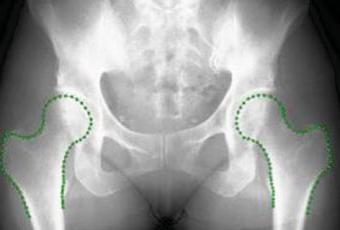

Una imagen del software Buscador de Huesos (Bone Finder) (Fotografía cortesía de la Universidad de Manchester). Hay escasez de radiólogos en el Reino Unido y, debido a la creciente necesidad de que los investigadores trabajen con grandes bases de datos de imágenes radiográficas, este software, desarrollado con financiación del Consejo de Investigación en Ingeniería y Ciencias Físicas del Reino Unido, ha sido diseñado para detectar automáticamente las formas de los huesos en las imágenes, en lugar de depender personalmente de los investigadores. Este sistema ya puede identificar las caderas. Sin embargo, los investigadores del Instituto de Salud de la Población de la Universidad de Manchester (Reino Unido) quieren modificarlo ahora para poder delinear las rodillas y las manos y así estar en capacidad de identificar otros huesos y estructuras internas del cuerpo. La financiación permitirá darle un mayor desarrollo, con lo cual se podrá llegar a asegurar que el sistema sea lo suficientemente exacto para utilizarlo en los hospitales con el fin de obtener un diagnóstico rápido de los problemas de los pacientes.

La financiación de 300.000 libras esterlinas dura tres años y se

basa en una investigación anterior que ayudó a desarrollar el

software, llamado Buscador de Huesos (Bonefinder), para

identificar los problemas y encontrar los contornos de las

caderas. Este software gratuito ha sido implementado por una serie

de grupos de investigación, entre ellos algunos con sede en Oxford

y en el estado norteamericano de California.